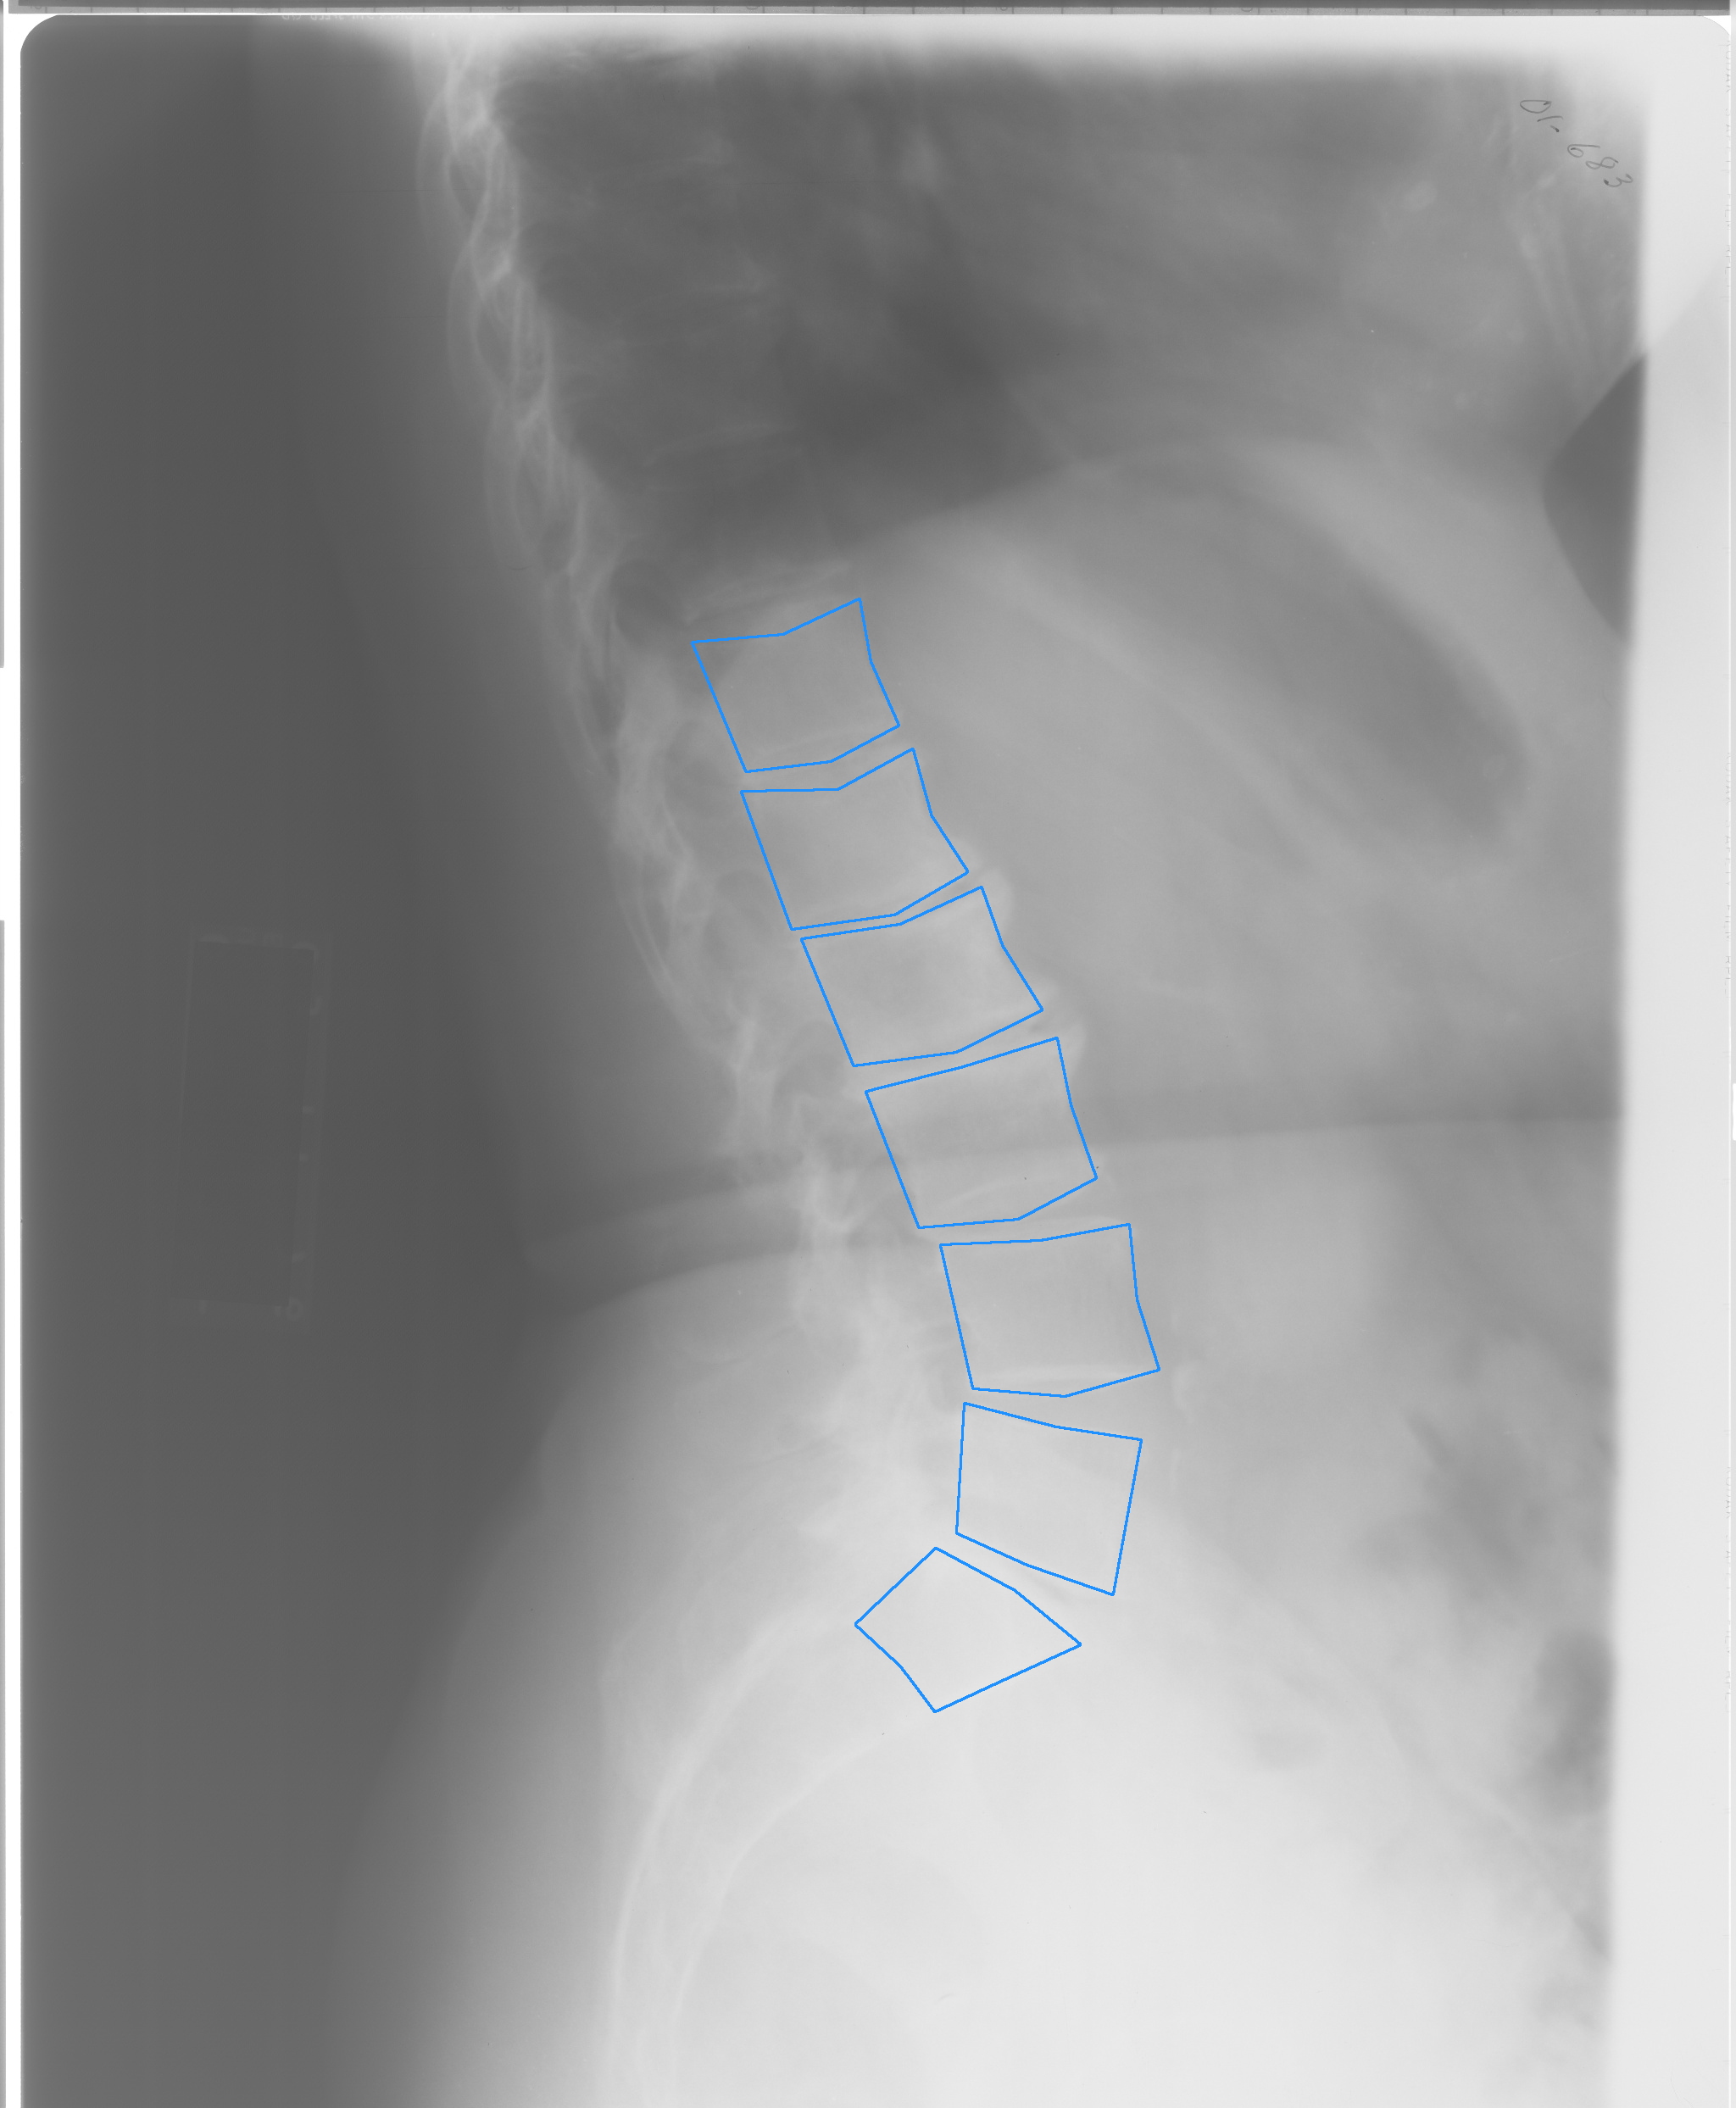

Fig. 1: Example X-ray images from NHANES II (left, center) and CSXA (right) datasets, with annotated vertebrae outlined in blue.

Our method was developed and tested using two publicly available datasets: the Second National Health and Nutrition Examination Survey (NHANES II) [10] and the Cervical Spine X-ray Atlas (CSXA) [11]. See Fig. 1 for example images.

(a) Low-contrast NHANES II image with reduced vertebrae clarity

(b) Poor-quality ground truth masks (e.g. squares) from CSXA dataset

Fig. 3: Examples of limitations related to each dataset, showcasing specific challenges encountered in spine X-ray segmentation

Tab 2 demonstrates that the robustness of our pipeline, achieving an average DSC of over 0.93 across most vertebra levels, with some levels even surpassing 0.96. Achieving such high DSCs is challenging due to inherent ambiguities in defining the exact boundaries within X-ray images. Furthermore, since each ground truth mask is constructed as a polygon from just seven landmark vertices, and so it may not perfectly represent the true shape of the corresponding vertebra (see Fig. 3(b)).

The main limitation of our method in the NHANES II test arose from imperfect vertebra identification, made apparent in the discrepancy between the Located DSC and Overall DSC. This issue occurs when the patch classifier misclassifies a new vertebra mask, leading to its rejection and the termination of the iterative process. Vertebrae at the ends of the spinal sections were particularly affected, especially T1 in the cervical section and T12 and L1 in the lumbar section. This misclassification is primarily due to inconsistent saturation levels between the X-rays, which can result in very poor contrast (see Fig. 3(a)). It is important to note that the NHANES II X-rays are digital scans of physical X-ray films. In contrast, digital X-rays offer superior clarity and contrast, which would mitigate this issue in a clinical setting. Our results on the CSXA dataset, which contains digital X-ray images, support this conclusion, as we successfully identified 99.5% of all labeled vertebrae.

While all CSXA X-ray images are of high quality and have consistent FOV, we observed a similar overall DSC to the NHANES II dataset, along with a decrease in the average DSC for the located vertebrae. We believe that this decrease is not due to a decline in segmentation performance but rather a consequence of the ground truth masks, which inadequately evaluate segmentation quality. Since the dataset only provides annotations for the vertebra corners, each mask is represented as a simple quadrilateral that does not accurately reflect the true shape of the underlying vertebrae. This limitation is evident in Fig.3(b). Consequently, the DSCs calculated from these masks do not truly represent the quality of our predictions.